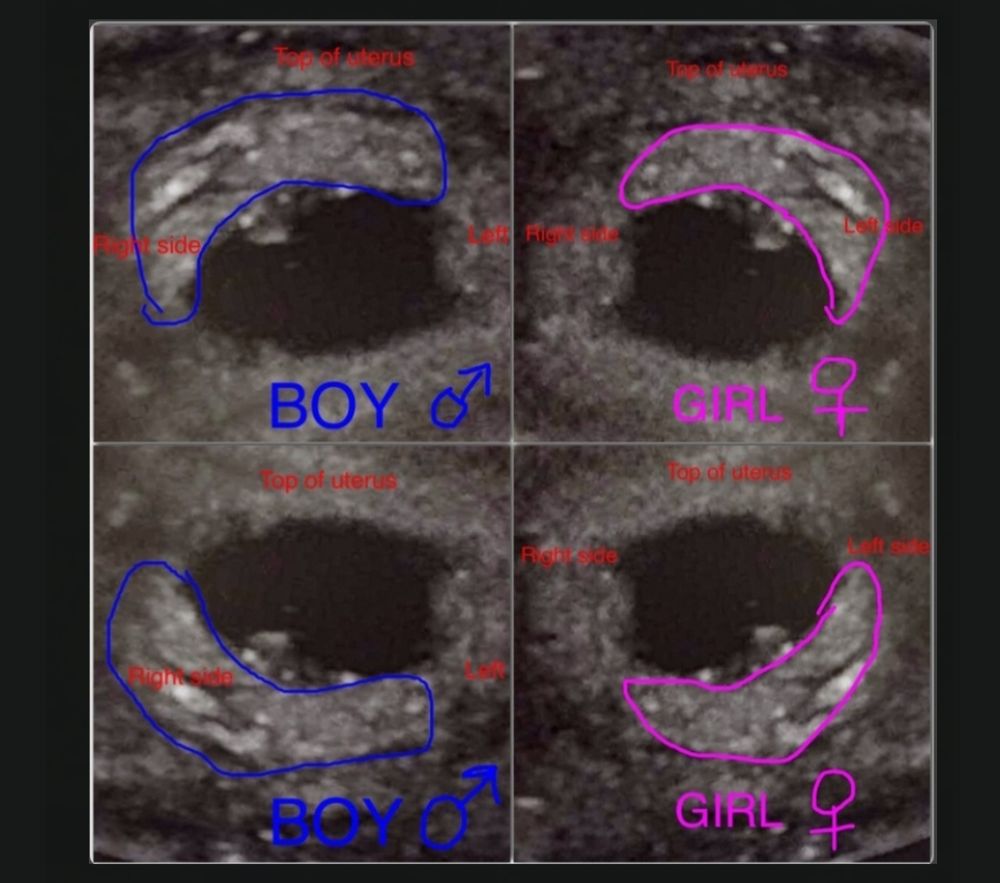

Метод Рамзи♀️♂️

По методу Рамзи у меня получается снова девочка, дочки также были справа по вагинальному фото с УЗИ, видимо со мной этот метод работает. Это фото в настоящую беременность в 5+6:

Может на следующем УЗИ получше будет видно, информативно по этому методу только в 6-8 недель.